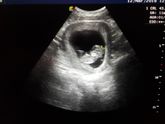

Девочки подскажите пожалуйста) у меня 12 неделя беременности, во всех источниках пишут что размеры малыша должны быть около 5 -6 см. А у меня УЗИ 12 марта (в понедельник ) показала что малыш уже 11 см .. у вас также было? Это Нормально? Подскажите по … Читать далее